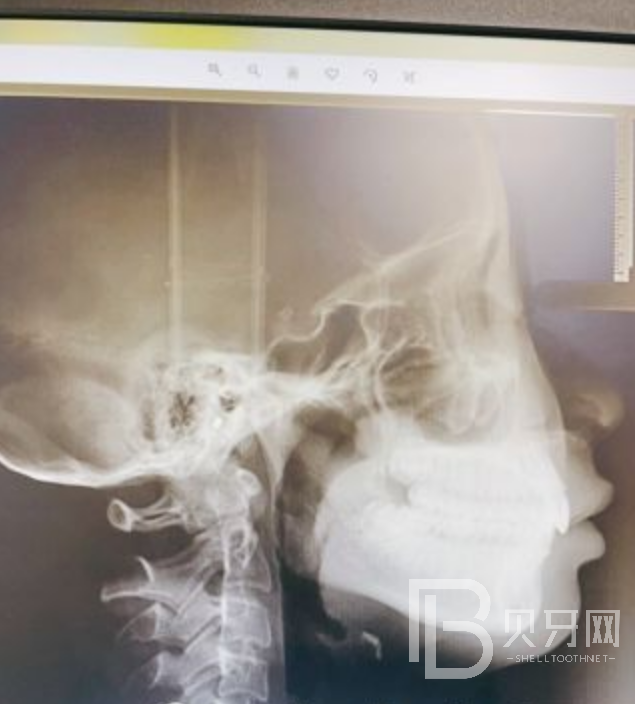

我是通过朋友介绍来瑞尔齿科找程医生来牙齿矫正,我是觉得我咬的很深,下牙看不到,在网上搜索了一下,我这个是叫深覆合,咨询了很多家牙科,也对他们说出了我的想法和预期,但是他们给的答案都不太让我满意,说是矫正完成后也没办法达到一个正常的覆合,正好身边有朋友是做过矫正的,给我推荐了瑞尔的程医生,也推了他的联系方式给我,我联系了他预约了时间过去看,到了诊所后护士姐姐带我拍了X光和口内照片,程医生看了我的口内情况和X光片,然后对着拍的数码照片对我进行了一个讲解,我也得到了我想要的答案,我这个深覆合是可以得到一个很好的改善的,听到这句话后立马我就下定决心开始矫正,给我和程医生签署了一份矫正的合同,取完了资料,听他的推荐我选择了隐形牙套,在和程医生沟通的过程中,医生的专业度,和他整个团队的态度都很让我踏实放心,让我认可,将牙齿交给他们,我很期待我的正畸之旅,期待良好的治疗效果;